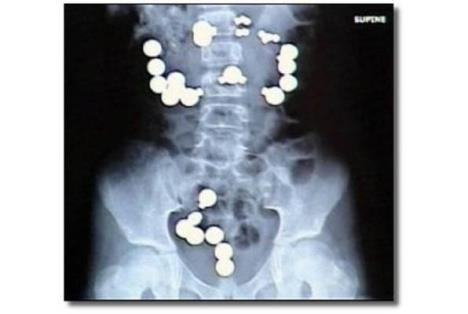

6. Stručno osoblje bolnice u Indijani ostalo je u najmanju ruku zabezeknuto kad su otkrili razlog misterioznog stanja jedne osmogodišnje devojčice. Devojčica je primljena zbog užasnih bolova u stomaku. Ono što se pregledom ustanovilo je da je devojčica progutala više od 30 magneta i metalnih predmeta. Na kraju je operacija prošla dobro, ali da su došli malo kasnije, pitanje je da li bi devojčica preživela.